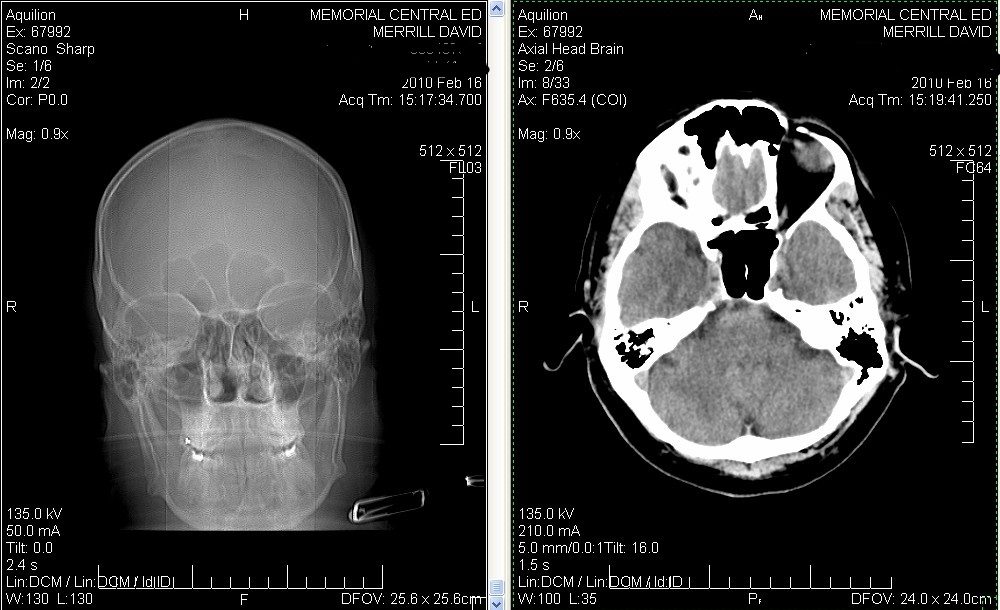

Click image for larger version

Name:	CAT Scan Pineal Gland.jpg

Views:	1

Size:	175.7 KB

ID:	42345